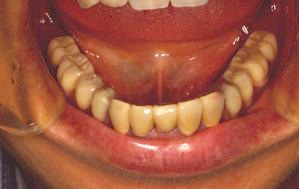

両側5歯症例

両側5歯症例両側5歯症例両側5歯症例 主訴-義歯のバネが壊れて手前の歯が痛んできた。 術前(旧義歯装着、鏡像) 術前(下顎粘膜面、鏡像)術前(下顎粘膜面、鏡像)術前(下顎粘膜面、鏡像) 術前レントゲン術前レントゲン術前レントゲン 術前口腔内(正面観)術前口腔内(正面観)術前口腔内(正面観)

術後(鏡像)術後(鏡像)術後(鏡像) 術後口腔内(正面観)術後口腔内(正面観)術後口腔内(正面観)もう入れ歯は要らなくなりました。 術後レントゲン術後レントゲン術後レントゲン